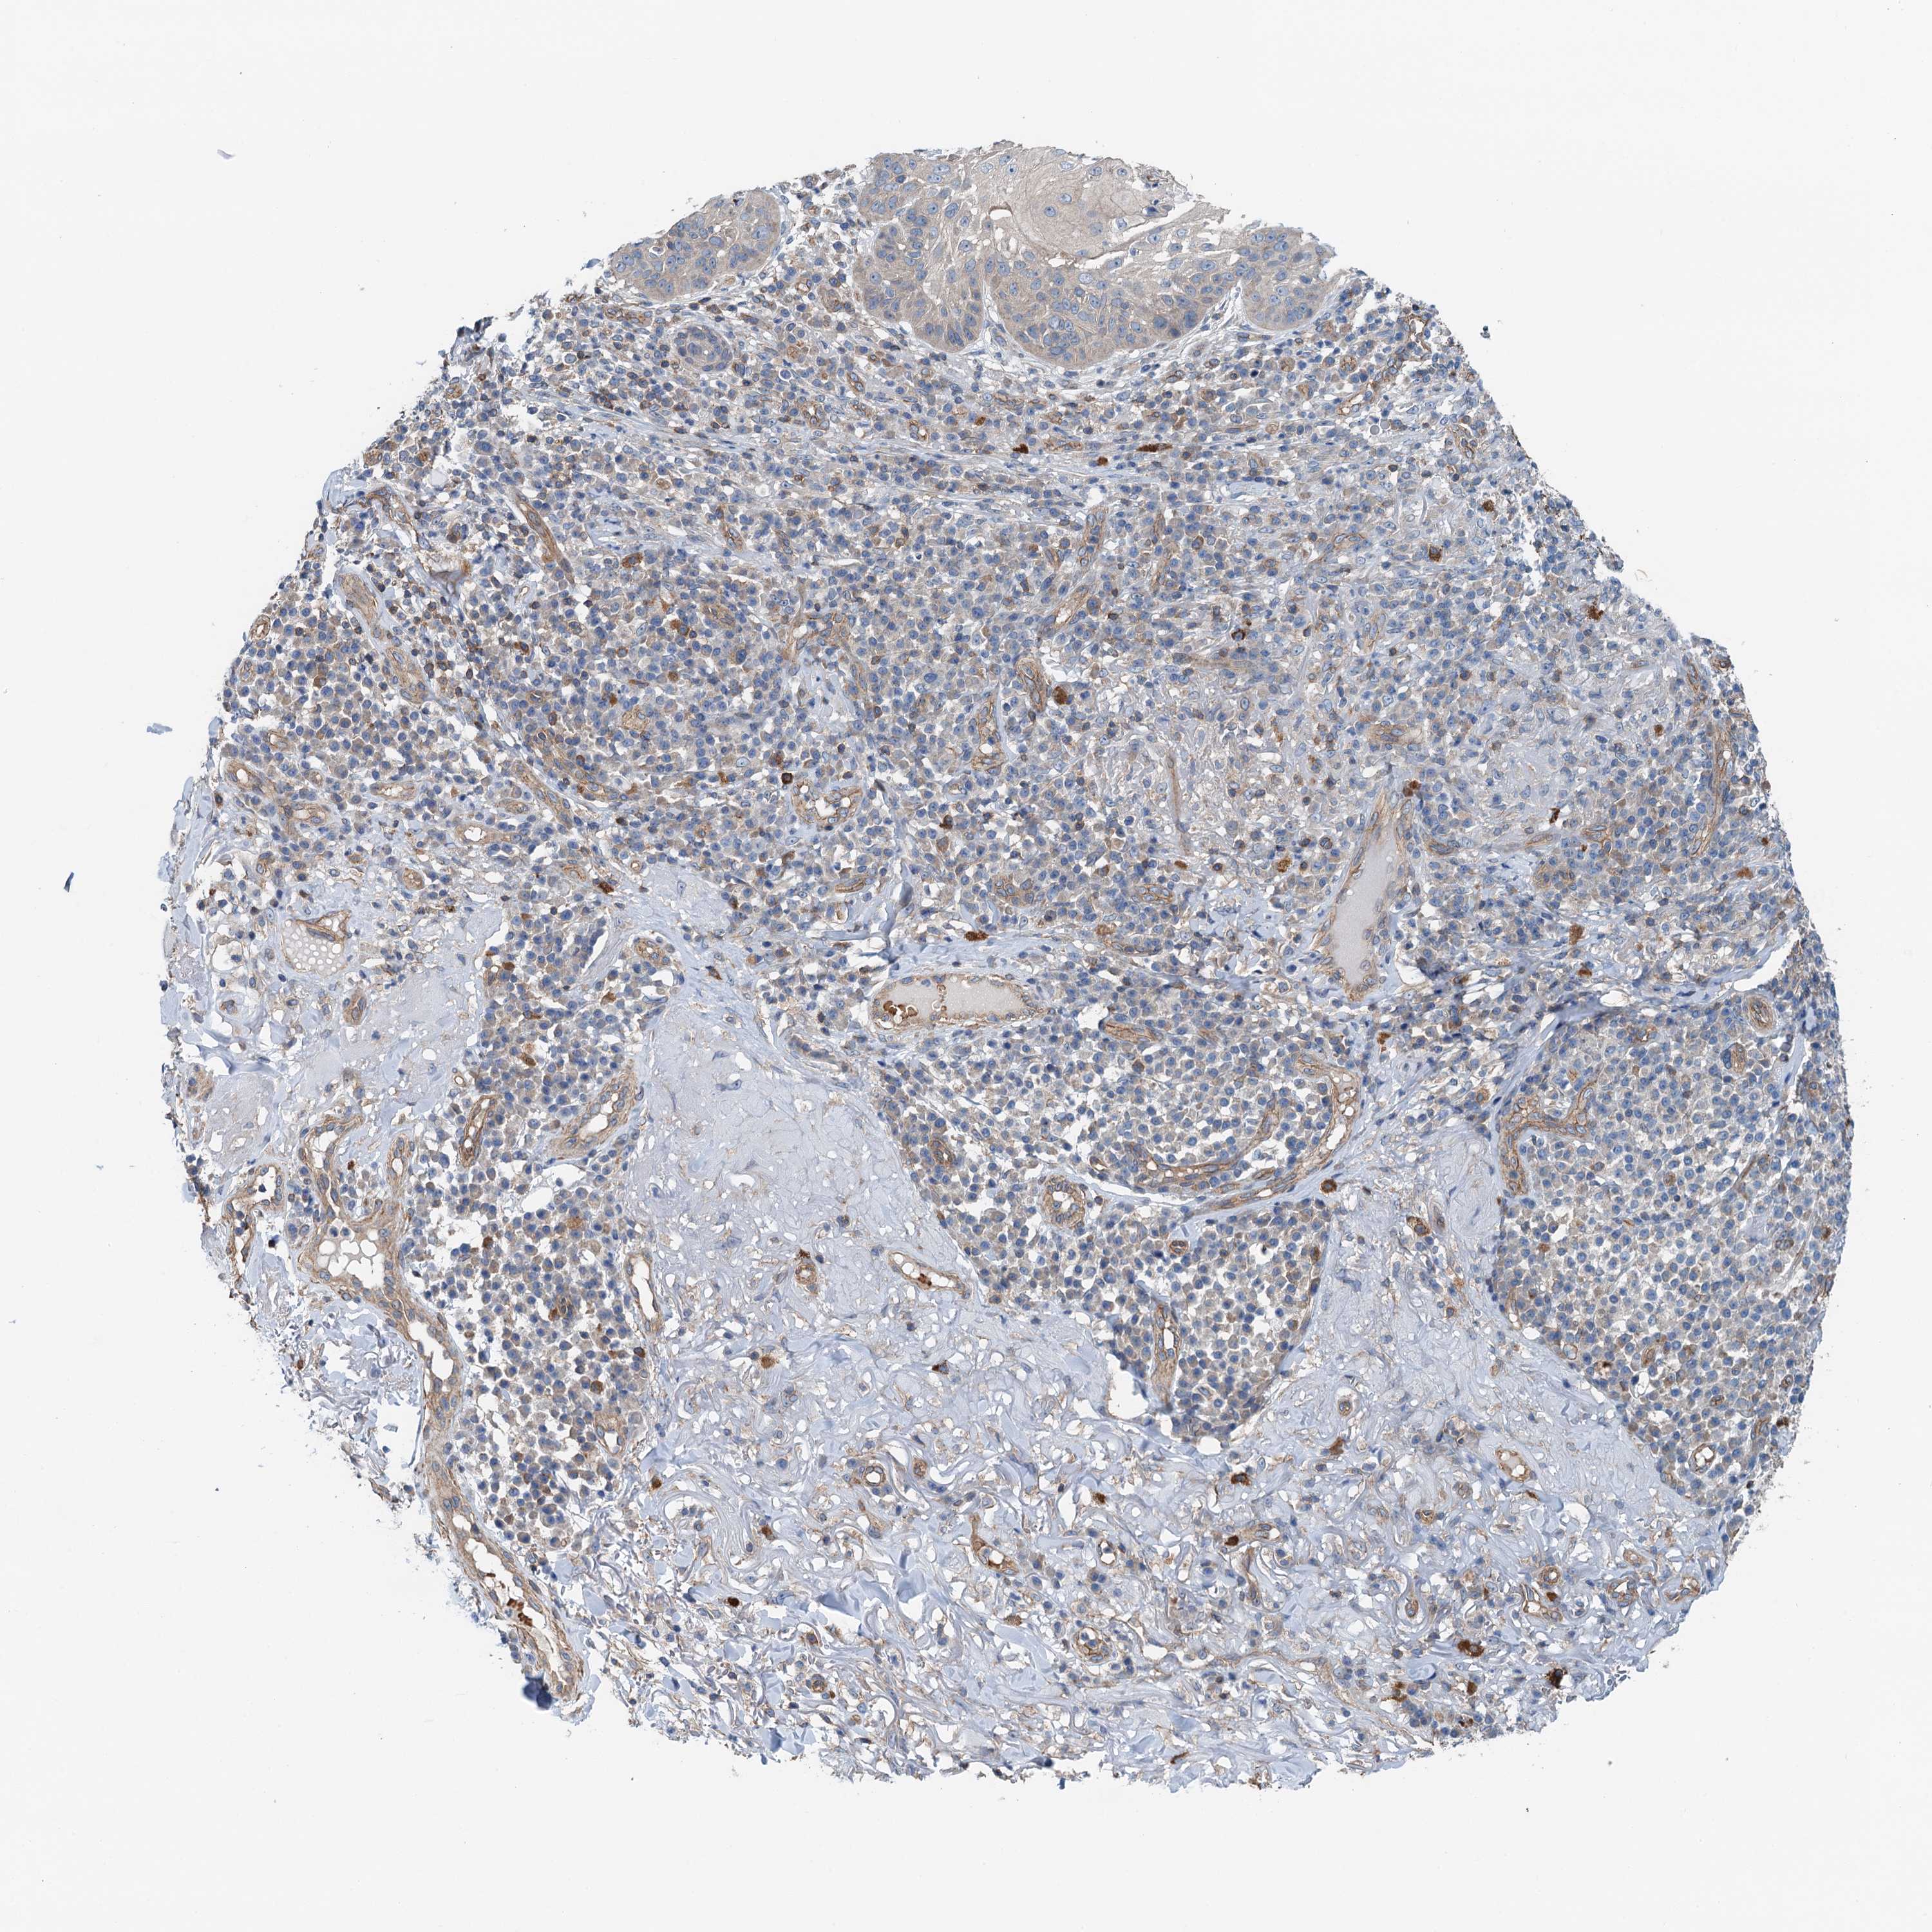

SKIN CANCER - Protein expressioni

A mouse-over function shows sample information and annotation data. Click on an image to view it in a full screen mode. Samples can be filtered based on level of antibody staining by selecting one or several of the following categories: high, medium, low and not detected. The assay and annotation is described here.

Antibody staining in the annotated cell types in the current human tissue is reported as not detected, low, medium, or high, based on conventional immunohistochemistry profiling in selected tissues. This score is based on the combination of the staining intensity and fraction of stained cells.

Each image is clickable and will lead to virtual microscopy that enables deeper exploration of all samples and also displays staining intensity scores, fraction scores and subcellular localization as well as patient and tissue information for each sample.

Antibody HPA041000

Staining

High

Medium

Low

Not detected

Intensity

Strong

Moderate

Weak

Negative

Quantity

>75%

75%-25%

<25%

None

Location

Nuclear

Cytoplasmic/membranous

Cytoplasmic/membranous,nuclear

Squamous cell carcinoma, metastatic, NOS